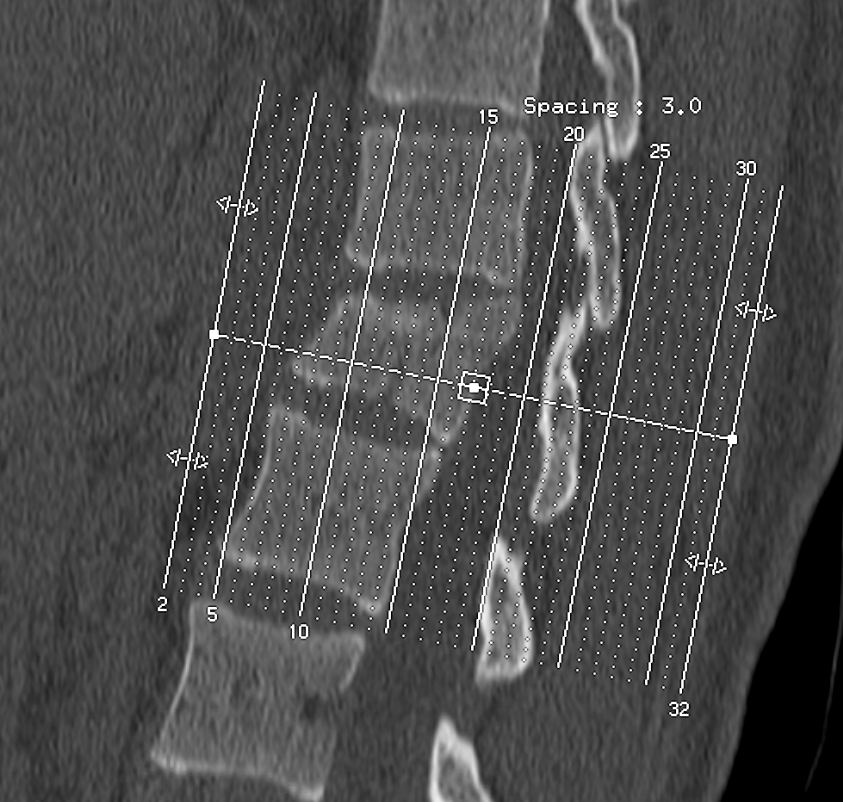

2. 척추 압박률 확인

다행히 수술할 정도가 아니라면 척추압박률을 확인해야 하는데요.

압박률은 골절된 척추를 기준으로 윗 척추의 길이와 아래척추의 길이를 구해서 평균을 낸 후

골절된 척추의 길이로 나누면 산출되는데

사진에서 보는 것처럼 척추는 사다리꼴 형태로 눌리기 때문에

어느 지점에서 길이를 재느냐에 따라 압박률이 달라집니다.

그리고 어느지점에서 길이를 재는지의 문제는

명시된 지침이 없기 때문에 의사의 고유권한이구요.

그래서 같은 척추골절에도 병원마다 압박률에 차이가 있을수 밖에 없습니다.